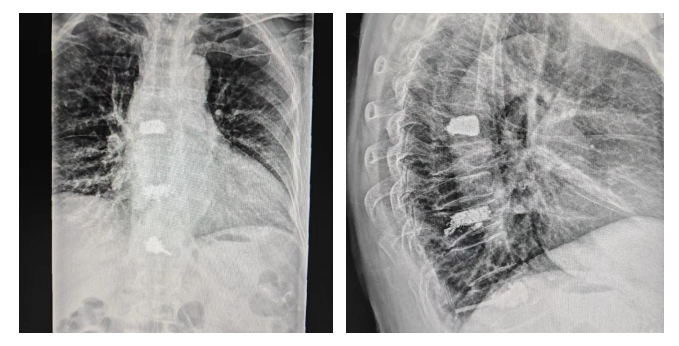

该例女性患者73岁高龄,为老年性骨质疏松症并胸12椎体压缩性骨折,术前患者腰背部疼痛剧烈,卧床翻身、下床活动困难。

术前外一科副主任宦忠甫、主治医师袁本曌等组成的医疗团队仔细分析了患者的X光片、CT成像,对患者的生活习惯进行深入了解,结合患者身体素质和病症情况,决定为患者实施经皮椎体成形术。手术在局部麻醉下进行,通过经皮椎体成形术穿刺针将骨水泥注入椎体,患者全程是清醒的状态,无任何不适感,仅用半个多小时顺利完成手术。